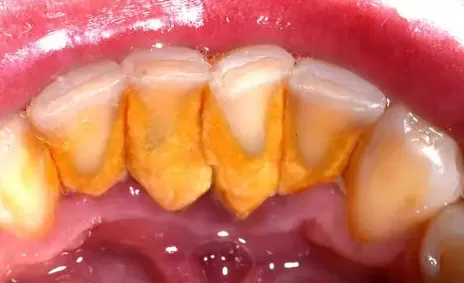

各位看官好,这里是建立在很久很久以前的资讯驿站,我是夏夏。关于牙结石是什么样的图片,应该很多网友想了解。网上很多相关的内容,这里做下整理汇总,仅做参考,有错误的还请指正。现在就来看看具体内容。牙结石是平时不注意口腔健康问题而导致的,这种长期积累下来的牙结石会危害到牙齿健康。很多人都不太懂牙结石是什么样子的,其实就是牙垢,牙齿内侧会比较明显。

牙结石是什么样的图片 牙结石是一种覆盖牙齿颈部的硬化刺激物,它通常是由一些牙菌斑缓慢沉积引起的。因此,需要及时治疗。牙菌斑含有一些细菌或物质,例如钙和磷酸盐。因为口腔唾液比较粘稠,很容易堆积在牙龈表面,会形成一些龈上牙石,如果堆积在牙龈下方,就会形成一些龈下牙石。 在这种情况下,需要通过超声波洁治或龈下洁治及时去除。一般来说,牙结石与牙菌斑很相似,只是看起来比较硬而且发黄,所以比较容易区分。需及时对症治疗,局部刺激物及时清除,方可缓解。一些局部炎症,缓解一些牙龈出血,以及牙龈退缩的发生。因此,牙结石的发生是非常可怕的,及时对症治疗可以有效缓解。